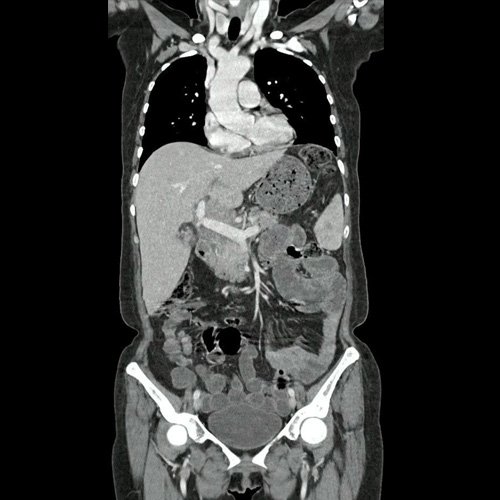

• Tomografía de abdomen y pelvis con contraste EV (DIA 2): Se visualiza esplenomegalia, con parénquima marcadamente heterogéneo, con áreas hipodensas focales mal definidas que se extienden por todo el órgano. La de mayor tamaño se observa en polo inferior y mide 14mm DT x 12mm AP. Hepatomegalia. Se visualiza parénquima hepático heterogéneo, visualizándose áreas pseudonodulares hipodensas en segmentos V y VI, destacándose la de mayor tamaño a este último nivel, subcapsular que mide 10mm DT x 19mm AP. Múltiples adenomegalias, algunas de ellas con tendencia a formar conglomerados, hiliares hepáticas y esplénicas, peripancreáticas, y retroperitoneales pre aórticas, destacándose una adyacente a la cabeza pancreática que mide 31mm DT x 20mm AP. Además se observan otras estructuras ganglionares aumentadas en número latero y retro aórticas. Se sugiere cotejar con datos clínicos, antecedentes y estudios previos recientes de la paciente de los cuales carecemos (linfoproliferativo?). La vía biliar intra y extrahepática es de calibre conservado. La vesícula biliar colapsada. Vena porta aumentada de calibre, mide 15mm, permeable. Circulación colateral periesplénica. El páncreas es de características normales. El conducto de Wirsung es de calibre conservado, sin efectos de masa. Las glándulas adrenales son normales. Ambos riñones son de forma, tamaño y situación habituales. Concentran y eliminan normalmente la sustancia de contraste, sin evidencia de alteraciones calicopiélicas ni ureterales. La aorta abdominal así como también las arterias ilíacas primitivas, internas, externas y femorales, son de calibre de trayecto flexuoso. Calcificaciones parietales. La vena cava inferior así como también las venas ilíacas primitivas, internas, externas y femorales, son de calibre y trayecto conservados. Contenido líquido en asas delgadas. Abundante materia fecal en colon transverso. La vejiga es de paredes lisas, sin presentar efectos de masa endoluminales ni parietales. El útero es de morfología y densidad conservada. No se observan alteraciones a nivel anexial. Se observan múltiples estructuras tubulares tortuosas en pelvis, en relación a varices pelvianas. No se observa líquido libre ni neumoperitoneo. Pequeña hernia umbilical sin complicaciones. Flebolitos pelvianos. Cambios artrodegenerativos a nivel de la columna dorso-lumbar.